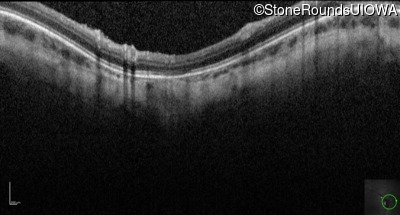

Optical Coherence Tomography - Right - 10/160 sc

Exemplar

Optical Coherence Tomography - Left - 10/200 sc

Exemplar / OCT Stack